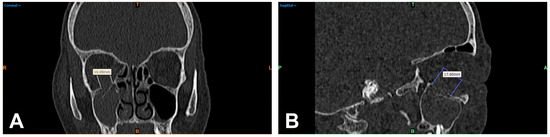

2.2. 2D-Based Measurement of Orbital Floor Fractures

2.3. 3D-Based Measurements of Orbital Floor Fractures